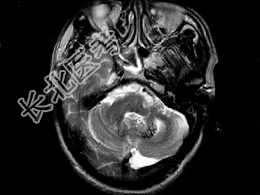

- 单项选择题男,49岁, 反复发作性癫痫,双手震颤5年, 伴头昏行走不稳,生化检查: 血清钙降低,血清磷升高, 请根据所提供图像,选择最可能的诊断 ( )

A、Fahr病

B、一氧化碳中毒性脑病

C、霉变甘蔗中毒

D、肝豆状核变性

E、甲旁低